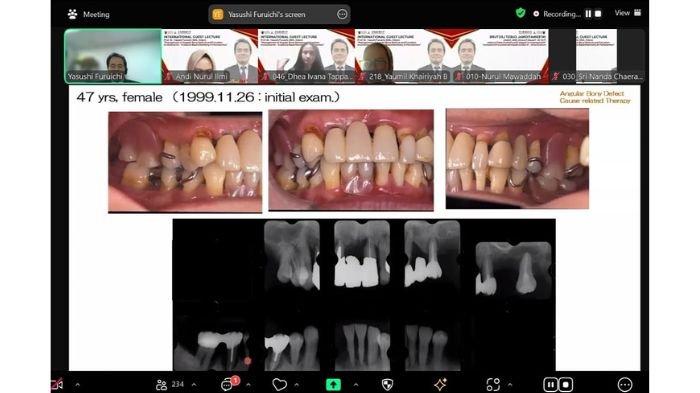

Mengangkat topik “Management of Angular Bony Defects and Furcation Involvements – Evidence-Based Dentistry in Periodontics”, kuliah ini merupakan bagian dari blok mata kuliah Penyakit Periodontal yang diperuntukkan bagi mahasiswa Kelas Internasional angkatan 2023.

Dalam pemaparannya, Prof. Dr. Yasushi Furuichi menjelaskan pendekatan berbasis bukti (evidence-based dentistry) dalam manajemen kerusakan tulang angular dan keterlibatan furkasi pada penyakit periodontal.

Beliau menekankan pentingnya memahami diagnosis secara mendalam, memilih terapi yang sesuai, serta memanfaatkan teknologi modern untuk meningkatkan keberhasilan pengobatan periodontal.

Prof. Furuichi juga menampilkan penanganan kasus-kasus penyakit periodontal.